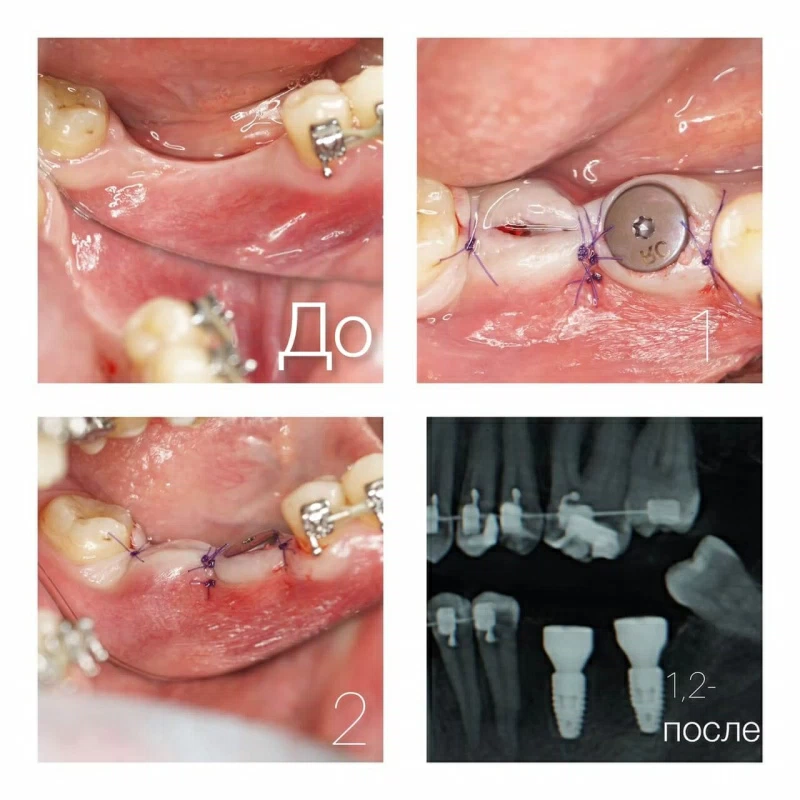

Фото до и после лечения

Наши работы